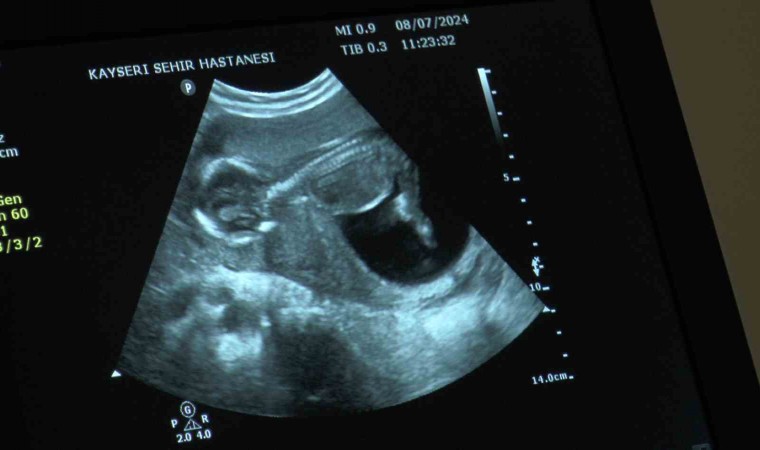

Doç. Dr. İlknur Çöl Madendağ,merkezde hastaya tedavi uygulamadan önce planlamaları yaparak bilgilendirdiklerini ve ortak karar ile tedavi uyguladıklarını söyleyerek, “Aslında hastalarımızın çoğu merkezimize tüp bebek yaptırma istemi ile gelmekte ama biz hastalarımızı değerlendirdikten sonra durumları hakkında ayrıntılı bilgi verip, tabi son tercihi onlara bırakmakla beraber, bilimsel veriler ışığında tıbbi durumu ne gerektiriyorsa öncelikle onu öneriyoruz hastalarımıza. Öncelikle tıbbi durumu hakkında hastalarımızı bilgilendirip önerimizi yapıyoruz ve onun isteği ile ortak kararımızı verip tedavimizi uyguluyoruz. Burada da hastamızın azalmış yumurtalık rezervi dediğimiz yumurta sayısı azlığı ve geçirilmiş dış gebelik, düşük, rahim tüp iltihabı, enfeksiyon durumları gibi sıkıntıları vardı. Bize geldiğinde önce ayrıntılı muayenesini yapıp gerekli tetkiklerinin ardından cerrahi müdahalesini planladık. Hastamızın azalmış yumurta sayısı vardı ama öncelikle rahim tüp filmini çektiğimize tüplerinde sıvı toplaması olduğunu ve kapalı olduğunu gördük. Yaptığımız ameliyatta tüpünün tıkalı olduğunu teşhis edip o sıvı toplamış tüpü aldık. Diğer tüpünün açık olduğunu gördükten sonra enfeksiyon tedavisini de yaptık. Yumurtalık gelişimini ve zamanlamasını ayarlayarak tüp bebek tedavisine gerek kalmadan gerekli antibiyotedavisini de verdikten sonra spontan gebeliğe 2 ay gibi kısa bir zaman içinde ulaştık. Geçirilmiş iltihabı vardı ve buna bağlı dış gebeliğinin oluştuğu yerde sıvı toplaması vardı. Bu da engel olan bir durumdu. Sonrasında hastamızın yumurta sayısını tekrar saydık. Gerekli destek tedavilerini verdik ve gebeliğine ulaştık. Şu an 16 haftalık gebeliği mevcut ve sağlıklı bir şekilde gidiyor” dedi.